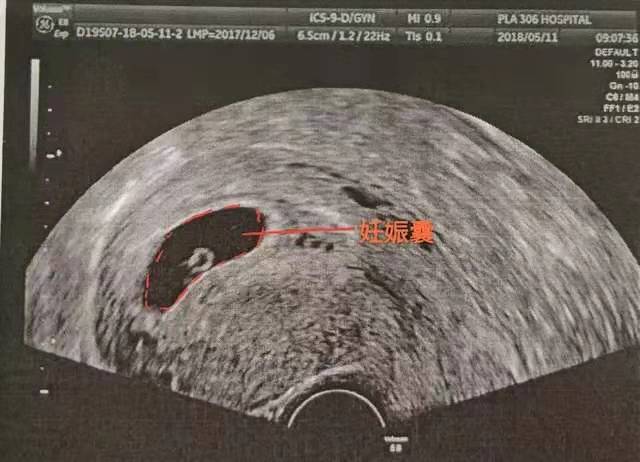

孕早期的胚胎往往会经历三步曲,我们就拿腹部超声来看好了,毕竟很多宝妈还是接受不了阴超(虽然也是安全的)。对于月经周期在28天左右的宝妈,一般怀孕6周左右可以在腹部超下看到孕囊。

怀孕7周左右在腹部超声下看到胚芽,甚至心搏。当出现心搏的时候,往往提示胚胎已经存活。